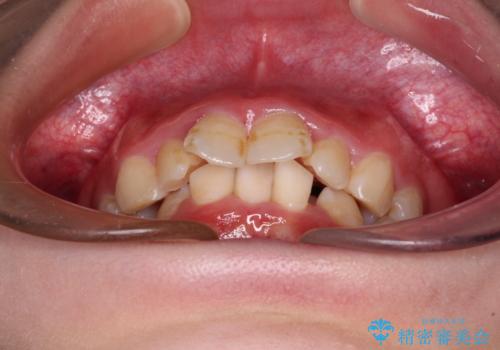

- 前歯のデコボコと唇の閉じにくさを気にして来院された患者様です。

極端な出っ歯という訳ではありませんでしたが、叢生が強かったため、上下左右の第一小臼歯4本を抜歯し、少しでも口元の突出感を改善できるよう治療計画を立案しました。

下顎前歯が隠れるほどのディープバイトであり、それによる顎の負担も大きかったため、ディープバイトもしっかりと改善できるよう、表側のワイヤー装置にて矯正治療を行うこととしました。